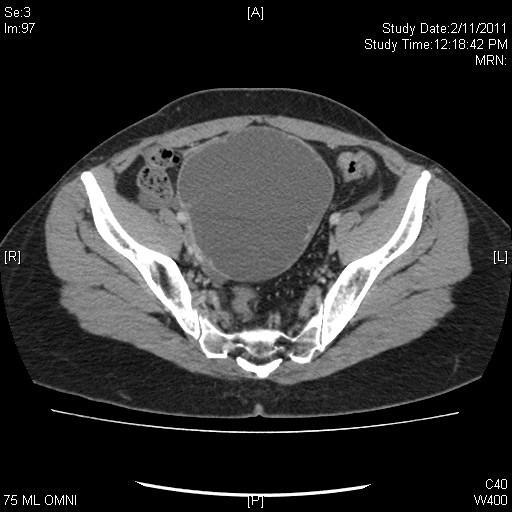

“Suspicious” masses

54yo (CA125=21)

Serous cystadenoma

48yo (CA125=104)

Endometriosis

47yo (CA125=47) Serous adenoca

32yo (CA125=20) Mucinous BT

21yo (CA125=21)

Serous BT